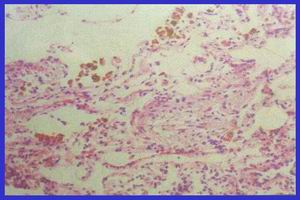

特發性肺含鐵血黃素沉著症2.光學顯微鏡檢查肺泡上皮細胞腫脹、變性、脫落和增生,肺泡腔內可見含有紅細胞或含鐵血黃素的吞噬細胞,肺泡壁彈性纖維變性,毛細血管增生,基底膜增厚,肺內小動脈彈性纖維變性,含鐵血黃素沉著,內膜纖維化、玻璃樣變。淋巴管周圍有淋巴細胞、漿細胞和含鐵血黃素巨噬細胞浸潤,淋巴管擴張。疾病後期可導致瀰漫性肺纖維化,肺氣腫,支氣管擴張等。

3.電子顯微鏡檢查廣泛的肺泡毛細血管損害,內皮細胞水腫,Ⅱ型肺泡上皮細胞增生,基底膜呈灶性破裂,蛋白沉積於基底膜,基底膜失去正常的結構。